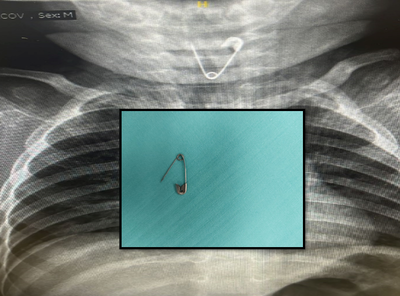

ניתוח חריג ומורכב התבצע בתחילת השבוע בבית החולים שיבא, אחרי שילדה בת שנה ושלושה חודשים הובאה למיון באמצע הלילה, כשהוריה חוששים שבלעה מחט | צילום הרנטגן חשף את החפץ החד בבסיס הריאה הימנית שלה, והוסר בהליך מורכב שנמשך דקות ספורות בלבד בבית החולים (בריאות)

ההורים שהגיעו אמש למיון ילדים באשדוד, סיפרו לרופאים כי הם חושדים שבנם בלע עצם זר, אך הם אינם בטוחים בכך, לאחר צילום רנטגן, התברר שהפעוט בלע סיכת ביטחון ונערך לו ניתוח חירום ודחוף (חדשות בריאות)